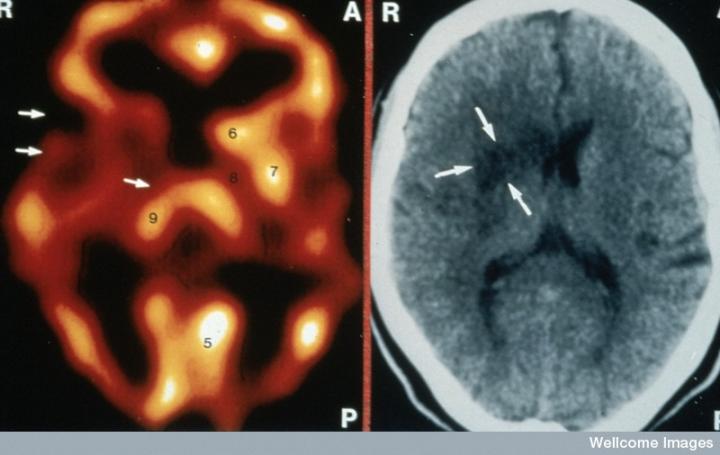

左侧的血流图比右侧的X射线CT扫描显示出更多的中风损伤

慢性中风患者的脑成像

CT扫描的主图显示左侧有一些中风损伤,由 Wellcome Images提供。Wellcome Photo Library提供的慢性中风的附加图像 ,Wellcome Images,QL 从胚胎干细胞培养的神经元。Ying & A. Smith, Wellcome Images 和 Yirui Sun, Wellcome Images 移植的小鼠神经干细胞。